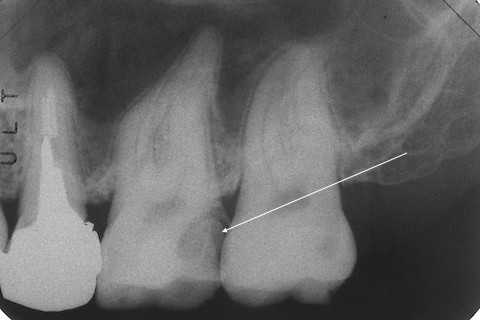

20代男性、咬合性外傷によるカリエス

今日は左上6の再建だ。口蓋遠心咬頭が破折した。しかも歯肉縁下まで破折しているので電気メスで歯肉を切り下げた。歯肉以外には麻酔は効かせていない。患者には申し訳ないが、健全象牙質をセンサー代わりに使った。痛みが出れば健全象牙質なのでこれ以上は削る必要がないと判断できる。

前回は神経が取られていたが、今回はそうではない。α-TCPセメントこそ使っていないが、前の先生は頑張ったと思う。

レントゲン写真